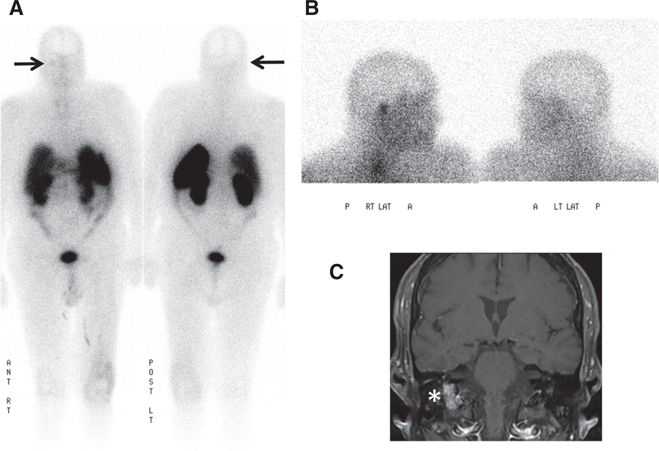

Fig 8

Figure 8 A 60-year-old woman with familial paraganglioma/pheochromocytoma syndrome status after right adrenalectomy with increased plasma metanephrine levels. (A) Previous whole body planar I-123 MIBG scan with attenuation-corrected SPECT, CT, and fused SPECT/CT images show increased uptake in multiple osseous lesions (white arrows). The patient was subsequently treated with I-131 MIBG therapy. (B) Ga-68 DOTATATE PET/CT maximum intensity projection (MIP) image of the skull vertex to the proximal thigh performed 5 years post-therapy because of increasing tumor markers shows widespread somatostatin receptor-positive bone metastatic disease with marked tracer uptake (arrows). (C) An F18-FDG PET/CT performed 1 week prior showed minimal to no uptake in corresponding osseous lesions.